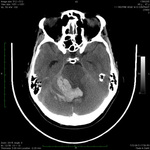

თავის ტვინის კომპიუტერული ტომოგრაფიის გამოსახულებაზე ჩანს ნათხემის ჰემორაგია, რომელიც მეოთხე პარკუჭში გადადის

ექიმი ს.ჰ. საბრამონის კოლექციიდან; გამოყენებულია მფლობელის ნებართვით